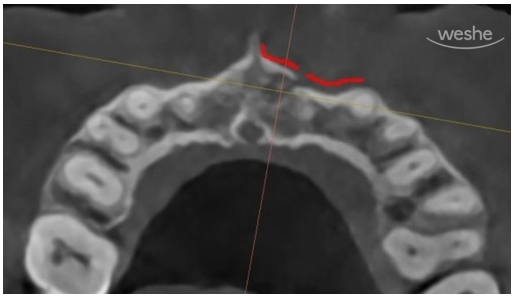

CT 사진입니다.

환자의 머리 위에서 바라보고 있는 방향입니다.

무엇이 보이나요?

노란선은 우리의 잇몸뼈 바깥경계선을 따라 그린 것입니다.

X-ray상에서 진한 흰색선으로 보이지요.

다른 부위에서는 잇몸뼈(치조골)가 연속적으로 잘 이어져 있는 반면,

빨간색으로 표시된 부위에서는 뼈의 윤곽선이 뚜렷하게 끊겨 있는 모습을 볼 수 있습니다.

이는 단순히 치아가 이동한 것이 아니라,

외상으로 인해 잇몸뼈 자체에 골절이 생긴 상황임을 의미합니다.

미국 근관치료학회(AAE)의 가이드라인에 따르면,

치아가 외상으로 잇몸 안쪽으로 밀려 들어간 경우라면

철사 고정은 2주 정도 유지하는 것으로 충분하다고 되어 있습니다.

하지만 지금처럼 잇몸뼈까지 골절이 동반된 상황이라면

고정 기간을 4주 이상으로 잡는 것이 권장됩니다.